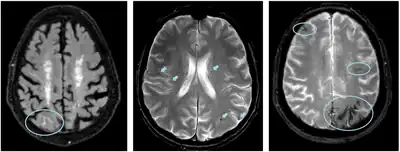

Left: ARIA-E with sulcal effusion (FLAIR sequence)

Middle: ARIA-H with multiple microbleeds (T2* weighted)

Right: ARIA-H with superficial siderosis (T2* weighted)